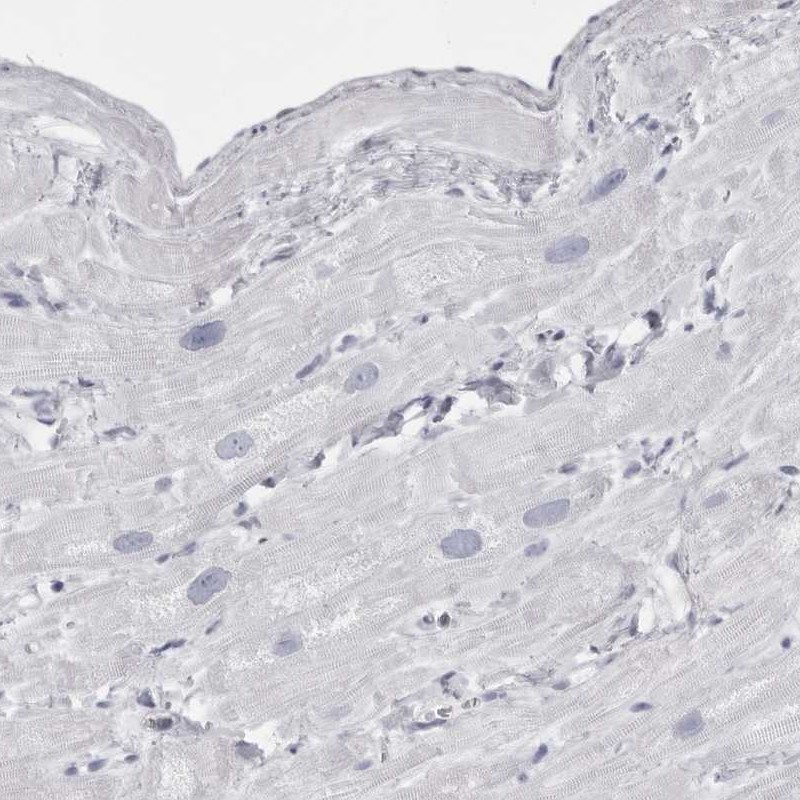

Immunohistochemistry analysis in human skeletal muscle and heart muscle tissues using Anti-TMOD4 antibody. Corresponding TMOD4 RNA-seq data are presented for the same tissues.